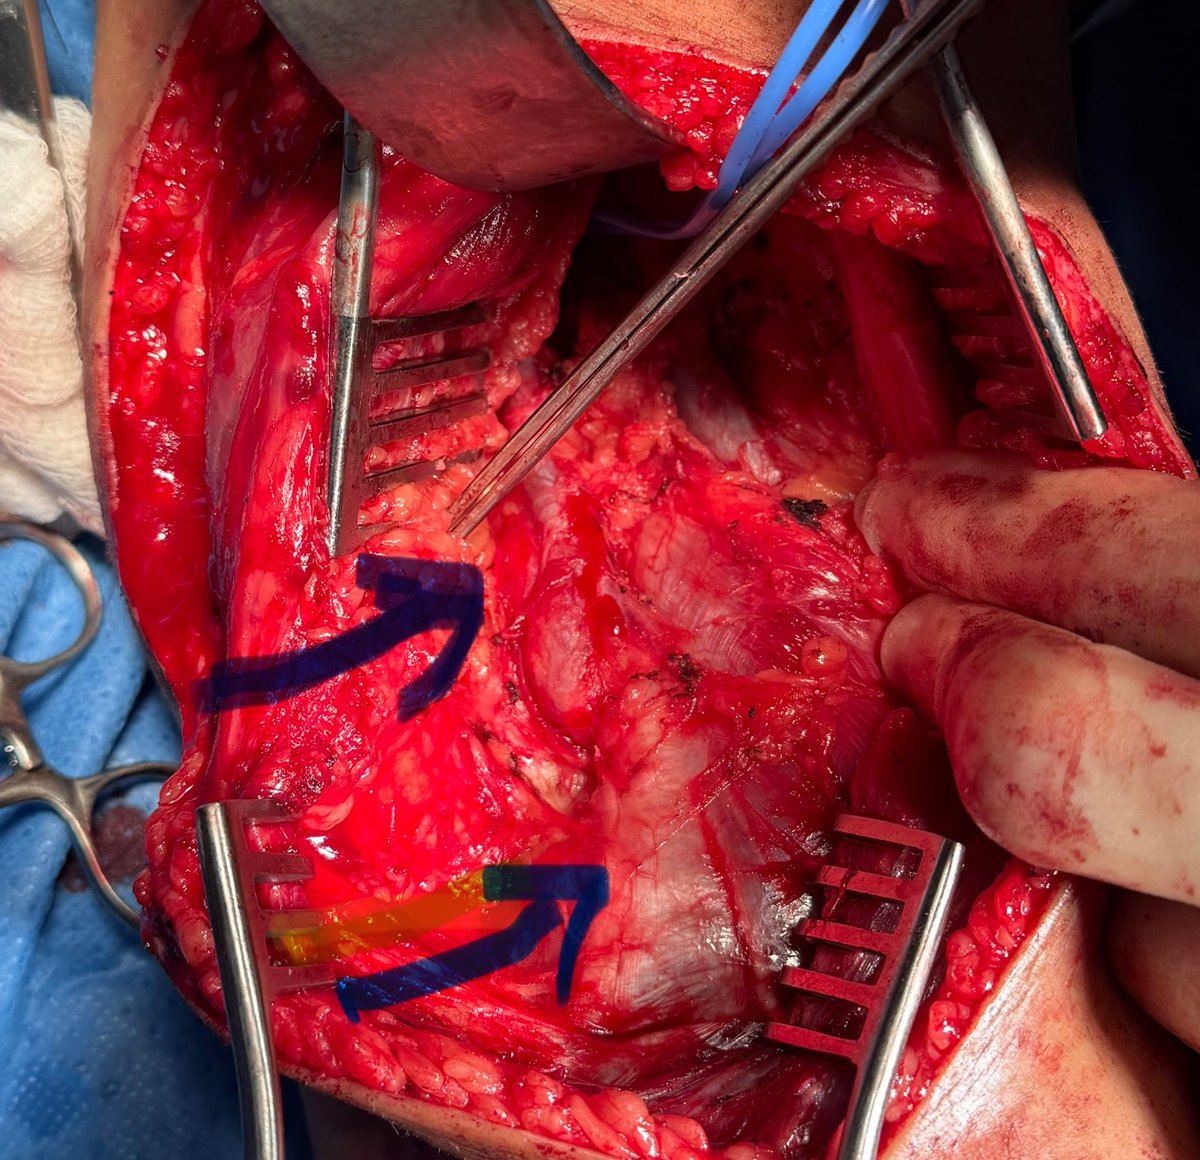

Diagnosis : Popliteal artery entrapment syndrome causing acute limb ischemia Intra-op pictures

#vasctwitter 17 yrs old male, keen football player.sudden onset pain in right leg and foot. Absent foot pulses and pale foot. CTA below. What is the diagnosis? Look at cross sectional image?! How would you treat?